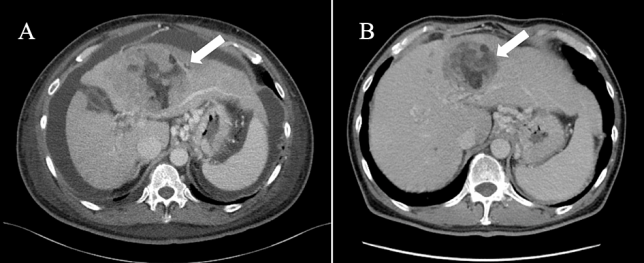

| NK细胞是一种天然免疫细胞,具有与T细胞完全不同的靶细胞识别方式,能泛特异性识别并杀死瘤细胞。NK细胞对肿瘤、病毒、寄生菌和机体老化变异细胞都具极强杀伤和清除能力。目前,NK细胞等免疫细胞疗法成为继手术、化疗、放疗和靶向治疗之后的第五种肿瘤治疗方法。01 、NK细胞联合疗法,让晚期肝癌患者脱离姑息治疗2024年8月5日,国际权威期刊《Cureus》发布了一项最新的临床案例分析,一名罹患晚期肝细胞癌(HCC)的患者,在接受了一种联合NK细胞治疗方案后,其肝功能得到明显改善,并且肿瘤体积也显著缩小,为后续治疗创造了有利条件。一位61岁的男性病患,既往存在丙型肝炎病毒感染,因腹部鼓胀症状入院,体内积聚超过3升的大量腹水紧急入院,被确诊为HCC T4N1M1 ⅣB期,伴有广泛的淋巴结转移、多发性肺部转移以及骨转移。因肿瘤导致的门静脉高压处于显著的腹水累积状态。检测结果揭示,患者淋巴细胞占比偏低,肝功能受损严重,且肿瘤标志物含量较高。鉴于其肝功能储备不良,仅能采取姑息性治疗手段,患者决定尝试联合新型免疫细胞疗法。研究团队制定了一套免疫治疗方案。首先,从脐带中分离出血液成分进行培养,经过14天的培养后,开始实施DC疫苗与纳武利尤单抗的联合治疗,前4个疗程每周一次,之后调整为每2周一次,共计7个疗程。同时,每3周进行一次NK细胞疗法,共3个疗程。经过3轮联合治疗,患者的体能状态有所好转,腹部紧张感明显缓解。在6个联合疗程后,患者的肝功能得到了显著提升,CT显示原发肿瘤及转移瘤的体积均有所减小,腹水完全消失。同时,治疗后患者的肿瘤标志物水平显著下降,维生素K缺乏诱导的蛋白-II也恢复正常范围。白细胞的整体状况及淋巴细胞比例均改善至正常。在肝功能得到改善后,于第7个联合疗程起开始接受标准治疗,进一步增强抗癌效果。02、 肿瘤术后进行NK细胞治疗,预防结直肠癌复发转移2023年7月,《Cancer Reports》期刊上公布了一则临床案例,一名患有结直肠癌的64岁女性患者接受NK细胞治疗2个周期后,复发转移停止进展。该案例是一位64岁女性患者,因横贯性结肠肿瘤引发的肠梗阻和血性腹泻就医。2018年12月,她接受了横结肠切除术,术后病理报告显示为横结肠腺癌,淋巴结受累阳性(III期),且肿瘤被完整切除(R0状态)。术后两个月,患者的癌胚抗原(CEA)水平为1.3ng/mL。她拒绝了辅助化疗,六个月后,PET-CT扫描显示间膜淋巴结葡萄糖摄取阳性,可能存在肿瘤复发。随后,患者接受了两个周期的NK细胞疗法,第二次治疗与第一次相隔三个月。在切除手术后三年,患者接受了PET-CT扫描随访。PET-CT扫描结果显示,未发现更多的葡萄糖摄取,患者对治疗的耐受性极佳,未报告任何与免疫相关的不良反应。在结肠癌根治性手术后三年的随访中,患者能够良好地适应日常活动,至今仍未出现局部复发的迹象和症状。在人体免疫系统的众多细胞“战士”中,NK细胞无疑是一位杰出的“抗癌英雄”,NK细胞无需预先激活,就能直接识别并消灭癌细胞,展现出强大的抗肿瘤作用。在这个不断发展的环境中,NK细胞疗法有望成为最有效的肿瘤治疗方式之一,肿瘤治疗不仅仅是一场战斗,而是一种个性化的、有针对性的、有效的治疗策略。